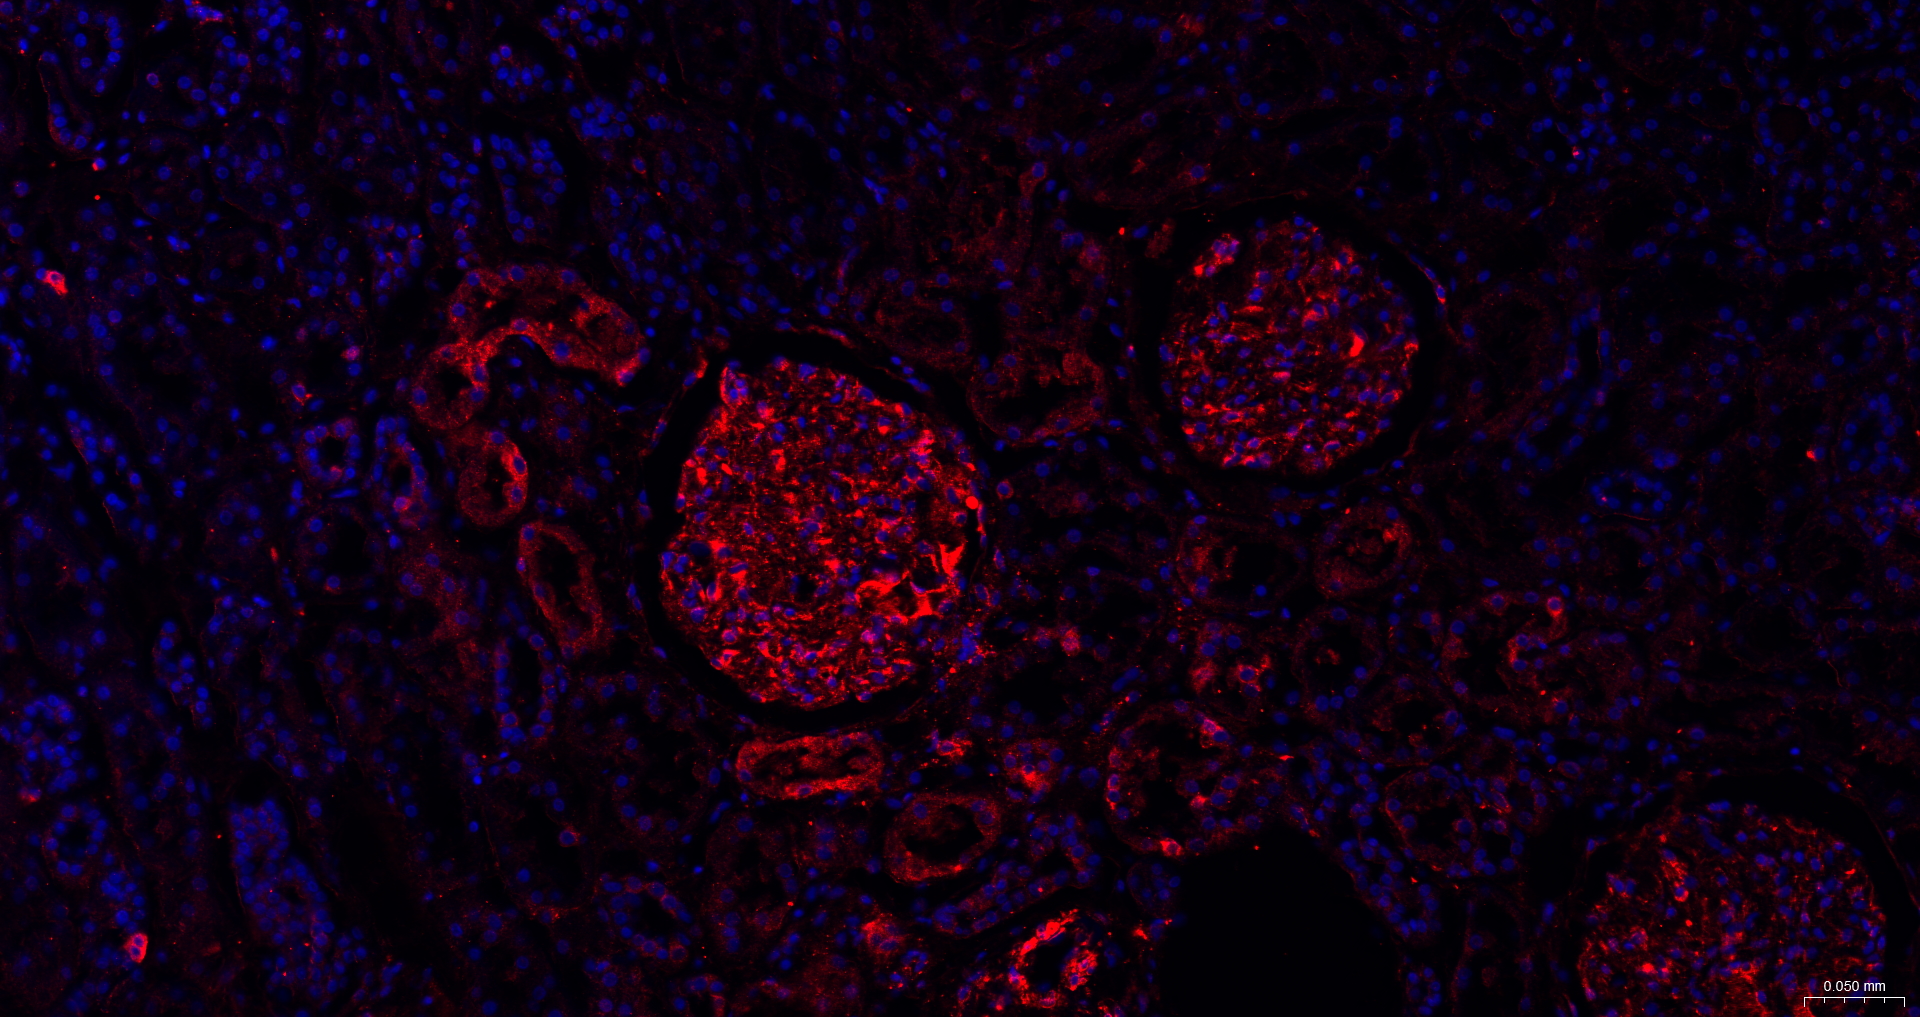

• IF(IHC-P)

IF(IHC-P) IFIHC-P1:100-500